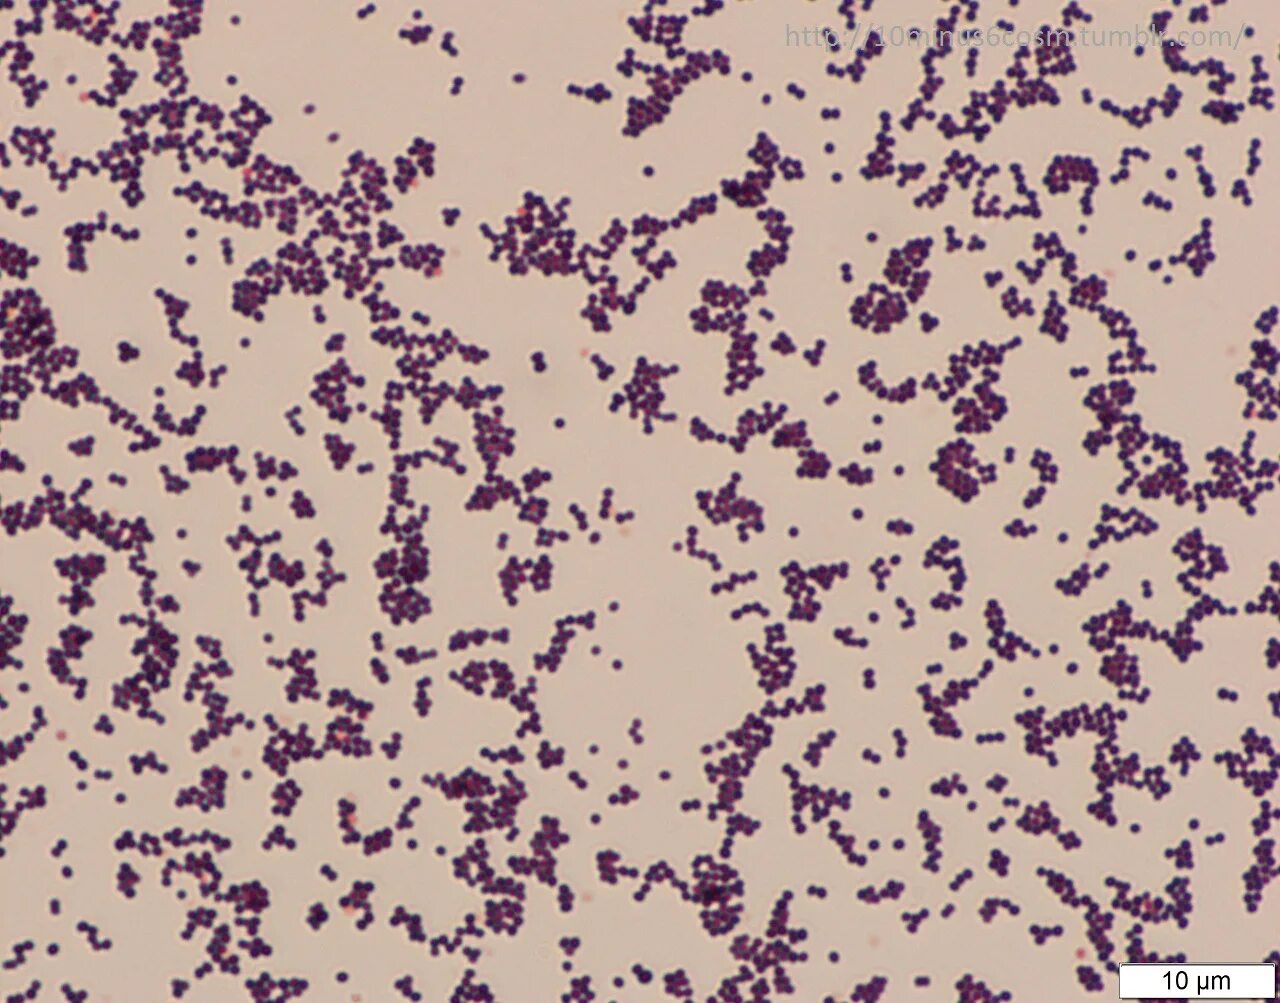

Стафилококк в мокроте